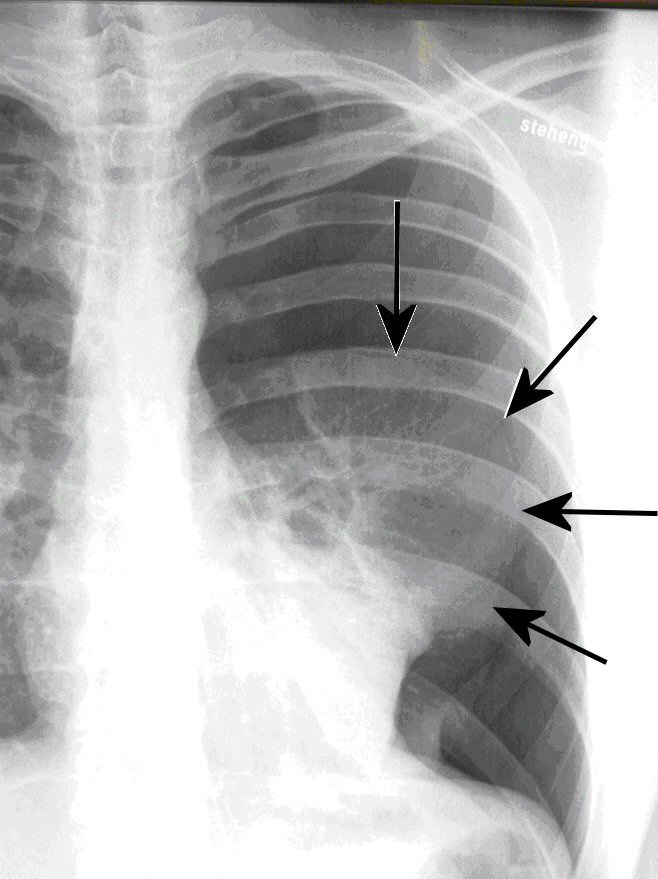

| Abb. 1: Spontanpneumothorax (Lungenkollaps) bei einem 25-jährigen schlanken Mann (die Pfeile zeigen den Rand der kollabierten Lunge) |

Jedoch ist ein Pneumothorax auch ohne Unfall möglich. Meist sind es junge schlanke Menschen, bei denen es zum Platzen einer angeborenen kleinen Blase (Bulla) an der Lungenspitze gekommen ist, die sich dann mit plötzlicher Luftnot bei uns vorstellen. Diese Diagnose wird mit einer computertomographischen Untersuchung bestätigt und vor allem im Fall des wiederholten Auftretens der kleine Lungenteil entfernt, der diese Blase trägt (Abb. 2). Dieser Eingriff wird in unserer Klinik fast ausnahmslos minimal-invasiv, d.h. in der "Schlüsselloch-Technik" vorgenommen. Anschließend muss der Rippenfellraum für wenige Tage über einen Schlauch besaugt werden.